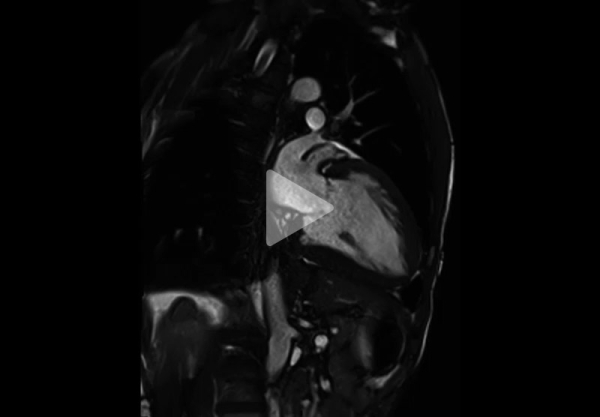

Vidéo 4 - Séquence Ciné-IRM coupe 2 cavités

Résultats de l’IRM cardiaque:

- Fonctions systoliques bi-ventriculaires conservées avec dilatation tétra-cavitaire

- HVG concentrique (masse VG à 128 g/m2 pour une normale < 90 g/m2) avec épaisseur maximale à 15 mm en antéro-septo-basal (Figure 7)

- Hypertrophie VD avec épaisseur diastolique à 5 mm (Figure 8)

- Hypertrophie des piliers mitraux (Figure 9) et trabéculations bi-ventriculaires

Aspects IRM évocateurs de maladie de Fabry :

Toute CMH, surtout si elle concentrique et si elle touche aussi le ventricule droit, doit amener à rechercher une maladie de Fabry ou une amylose cardiaque

- Toute CMH, surtout si elle concentrique et si elle touche aussi le ventricule droit, doit amener à recherche une maladie de Fabry ou une amylose cardiaque